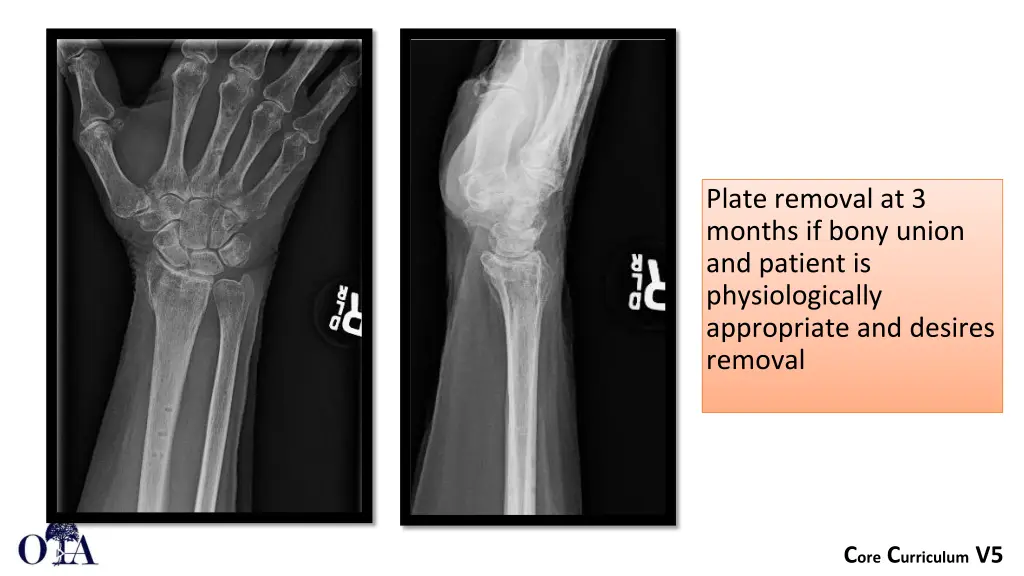

Plate removal at 3 months if bony union and patient is physiologically appropriate and desires removal Core Curriculum V5